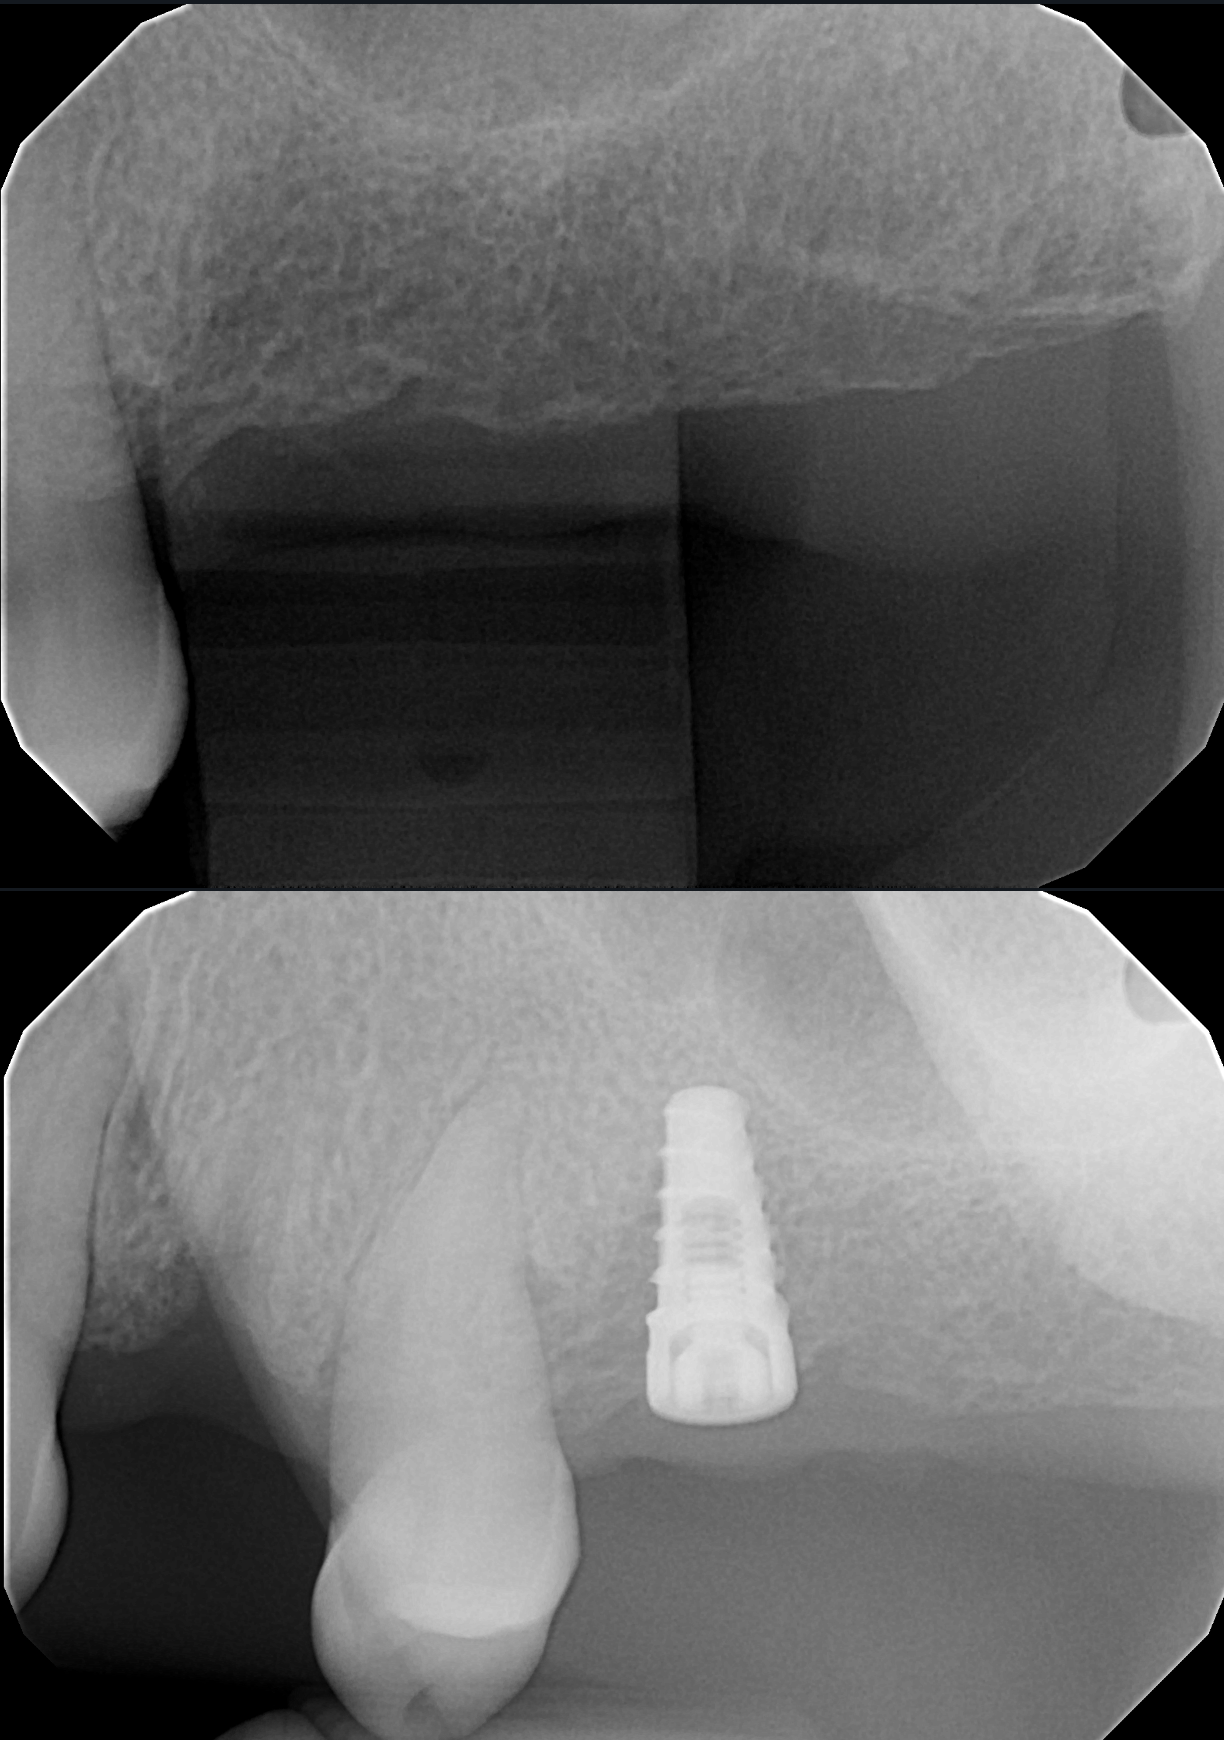

A selection of before and after X-ray images from cases I have performed, showcasing single implants placed in posterior gaps and single-tooth spaces. This is often the ideal solution in these situations.